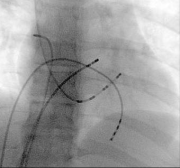

Diagnostic Electrophysiology Study (EPS)

I have experience of diagnostic electrophysiology study in patients with heart rhythm disorders. This can tell us more about the heart rhythm problem and whether it is dangerous. Often this is part of a therapuetic procedure, catheter ablation (see below). Electrophysiology study (EPS)

Diagnostic electrophysiology study ("EPS")